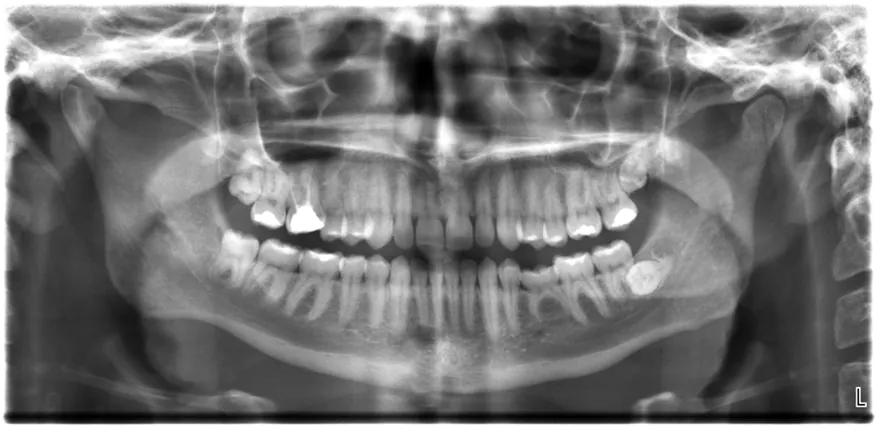

All of us can identify diagnostic uses of x-ray photons. Among these are the universal dental and medical x rays that have become an essential part of medical diagnostics. (See Figure 30.23 and Figure 30.24.) X rays are also used to inspect our luggage at airports, as shown in Figure 30.22, and for early detection of cracks in crucial aircraft components. An x ray is not only a noun meaning high-energy photon, it also is an image produced by x rays, and it has been made into a familiar verb—to be x-rayed.

The X-ray image of front view of the jaw, especially the teeth.

Figure 30.22 An x-ray image reveals fillings in a person’s teeth. (credit: Dmitry G, Wikimedia Commons)

The most common x-ray images are simple shadows. Since x-ray photons have high energies, they penetrate materials that are opaque to visible light. The more energy an x-ray photon has, the more material it will penetrate. So an x-ray tube may be operated at 50.0 kV for a chest x ray, whereas it may need to be operated at 100 kV to examine a broken leg in a cast. The depth of penetration is related to the density of the material as well as to the energy of the photon. The denser the material, the fewer x-ray photons get through and the darker the shadow. Thus x rays excel at detecting breaks in bones and in imaging other physiological structures, such as some tumors, that differ in density from surrounding material. Because of their high photon energy, x rays produce significant ionization in materials and damage cells in biological organisms. Modern uses minimize exposure to the patient and eliminate exposure to others. Biological effects of x rays will be explored in the next chapter along with other types of ionizing radiation such as those produced by nuclei.